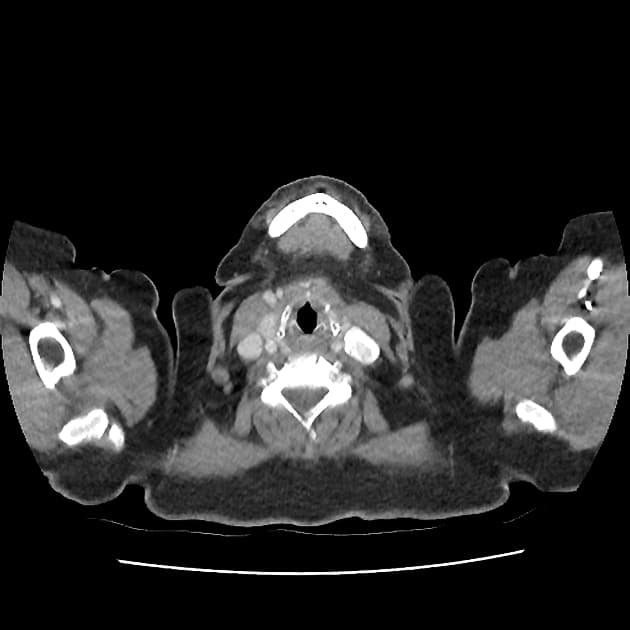

Acute appendicitis in pregnancy (MRI)

Thai 28 tuần, xuất hiện đau hạ sườn phải mới khởi phát.

Quan sát thấy một cấu trúc dạng ống giãn ở vùng hạ sườn phải, kèm tăng tín hiệu T2 xung quanh, gợi ý phù nề và viêm quanh cấu trúc này. Ngoài ra, ghi nhận một viên sỏi trong túi mật.

THẢO LUẬN: Đây là trường hợp viêm ruột thừa cấp ở bệnh nhân mang thai. Sau khi chụp MRI, bệnh nhân đã được phẫu thuật cắt ruột thừa mở, với theo dõi tim thai trước và sau phẫu thuật. Kết quả giải phẫu bệnh cho thấy: Ruột thừa to và giãn Thanh mạc màu xám sẫm đến nâu đỏ Có hiện tượng dính Dịch tiết nhầy mủ lan tỏa Lòng ruột thừa: Giãn Thành dày Các đặc điểm này phù hợp với chẩn đoán viêm ruột thừa cấp trên hình ảnh học. Bệnh nhân dung nạp phẫu thuật tốt, không có biến chứng và hồi phục thuận lợi. Ý nghĩa lâm sàng quan trọng: Trường hợp này nhấn mạnh rằng các bác sĩ lâm sàng và bác sĩ chẩn đoán hình ảnh cần luôn nghĩ đến viêm ruột thừa ở bệnh nhân mang thai có đau hạ sườn phải, vì: 👉 Tử cung mang thai có thể đẩy ruột thừa lên cao, làm thay đổi vị trí giải phẫu bình thường. Điều này có thể gây: Chẩn đoán chậm trễ Hoặc nhầm với bệnh lý gan mật Đồng tác giả: Amira Elfergani

Viêm ruột thừa cấp trong thai kỳ (chụp cộng hưởng từ)